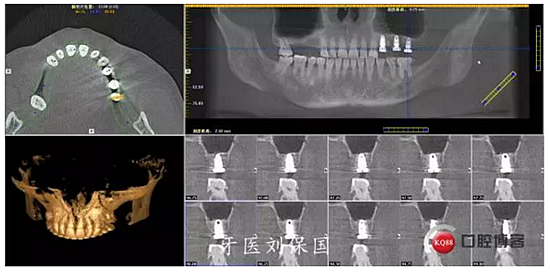

4.六個月后二期CT: